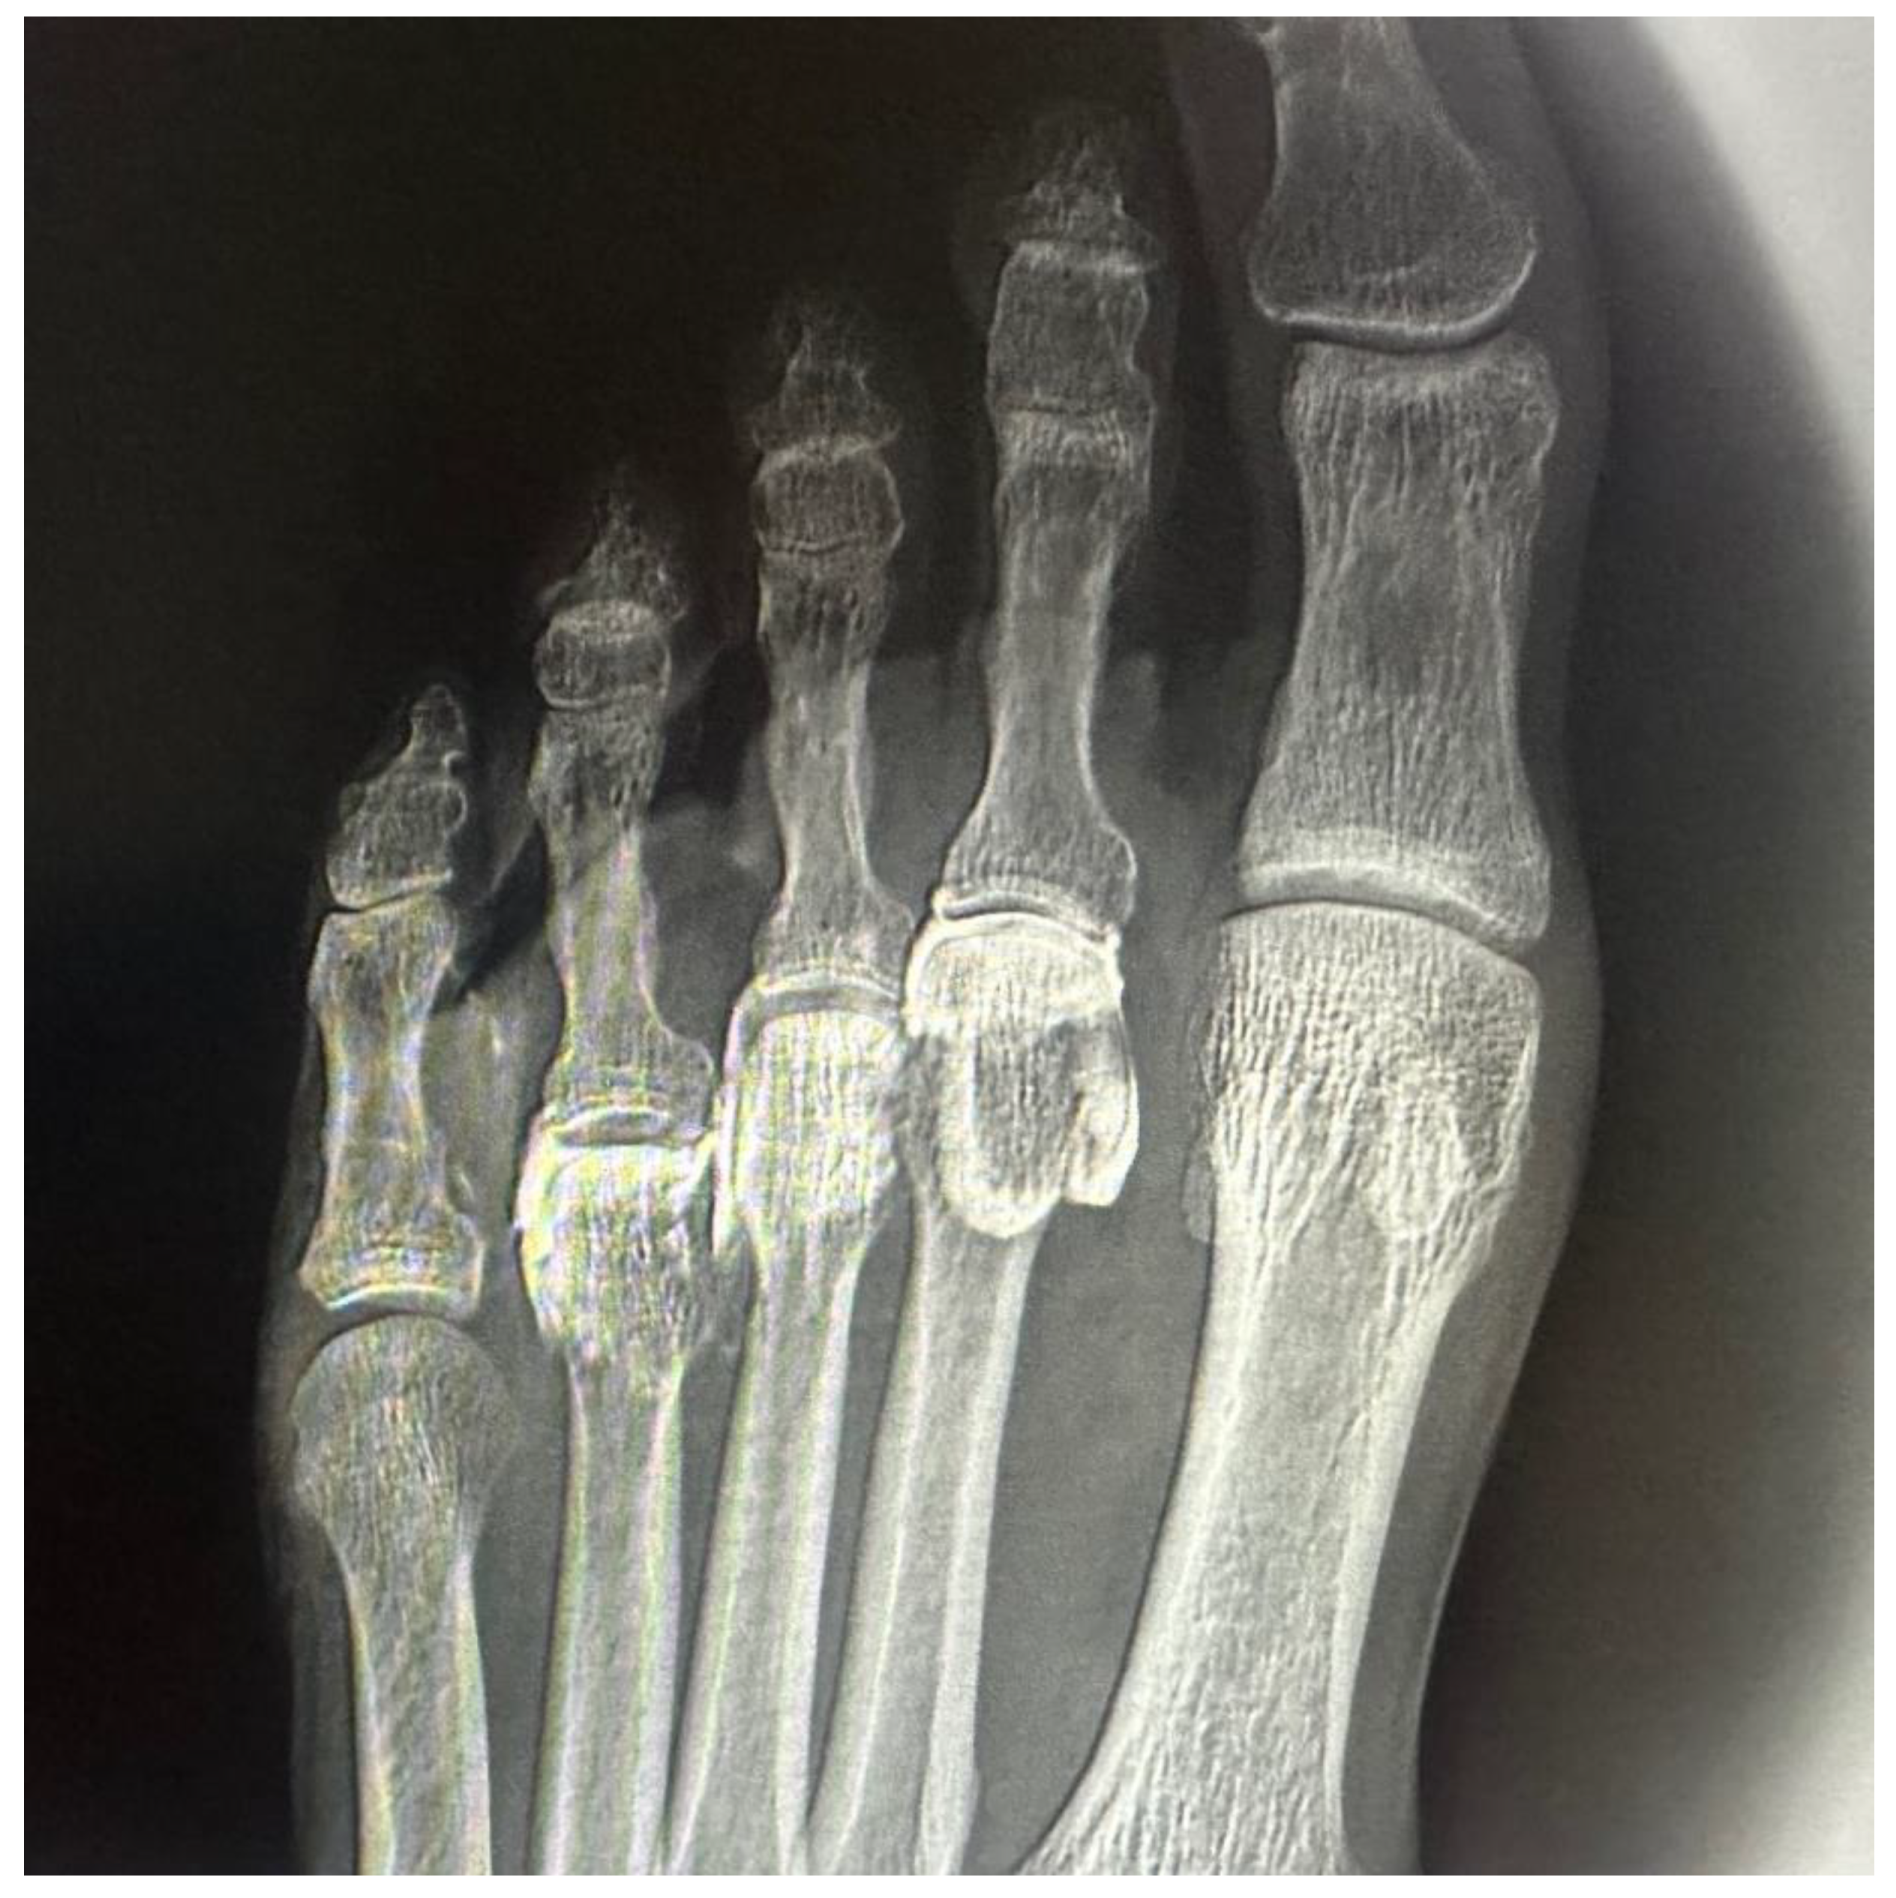

In all specimens, IM space infiltration resulted in diffuse, uncontained dispersion with irregular expansion and poorly defined borders (Figure 3). The contrast extended both proximally and laterally into adjacent soft tissue planes, following fascial paths with no clear anatomical containment. Additionally, a tendency for contrast migration toward the plantar region was observed, following the trajectory of the common plantar digital nerve. The mobility and superficial location of this nerve within the IM space appear to facilitate the lack of containment. This pattern confirms that the IM space functions as an anatomically open cavity with higher permeability to infiltrated fluid.

Figure 3. Ultrasound-guided injection of 0.5 cc of radiopaque contrast targeting the third common plantar digital nerve. The injection was performed in long axis, with a distal-to-proximal trajectory parallel to the nerve. A) Dorsoplantar projection of the right forefoot. B) Oblique projection of the same injection, allowing better visualization of the contrast tracking along the interdigital space.